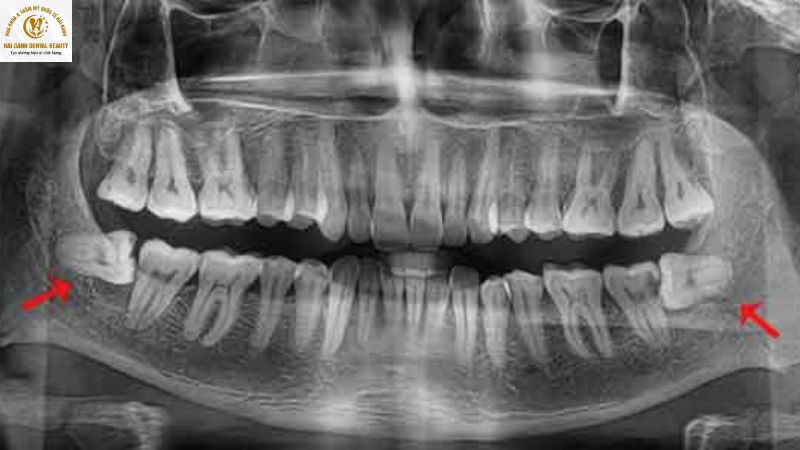

Răng khôn là nhân tố quyết định trực tiếp. Nếu răng khôn mọc lệch, đâm xiên vào răng số 7 (răng hàm lớn thứ hai), hoặc mọc ngầm dưới xương hàm, nó sẽ gây xô lệch cả cung hàm, ảnh hưởng đến toàn bộ quá trình niềng. Trong những trường hợp này, việc nhổ răng khôn trước khi niềng là bắt buộc và cần được ưu tiên hàng đầu.

Răng khôn mọc lệch, ngầm, ngang có thể sẽ làm ảnh hưởng để răng số 7